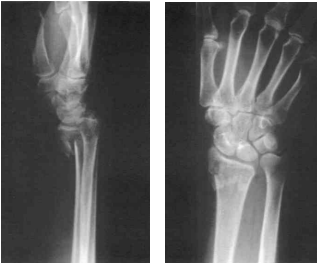

60 64 歲何太太某日於菜市場滑倒,右手撐地後立即疼痛腫脹難忍。醫師立即作了 X 光檢查,發現其 X 光片如圖所示,則此種傷害一般稱為:

(A) 柯利氏骨折(Colles’fracture) (B) 蒙太奇骨折(Monteggia fracture) (C) 瓊斯骨折(Jones fracture) (D) 葛立茲骨折(Galeazzi fracture)